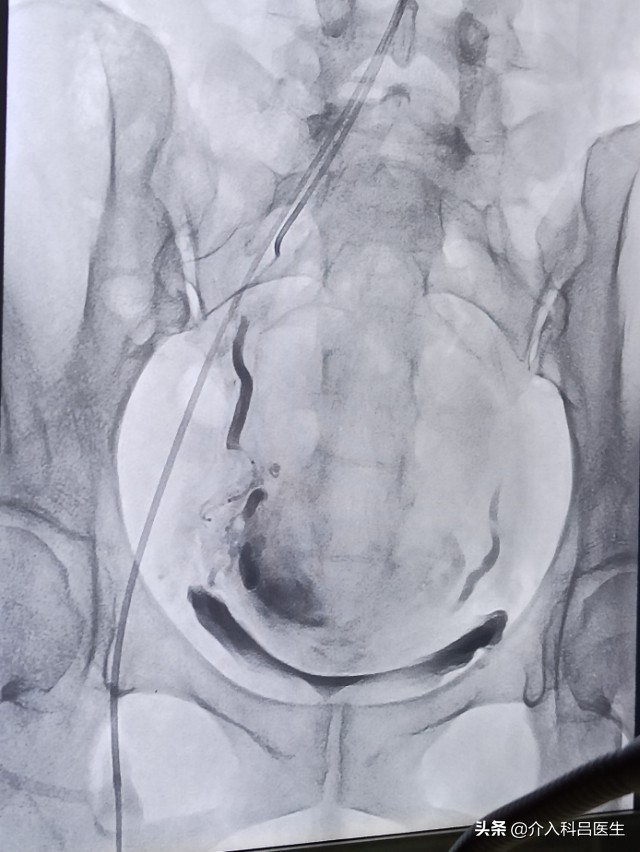

这是一种超选择性子宫腺肌症血管床栓塞术,经皮穿刺将1 毫米~2 毫米粗的导管送入子宫动脉,使导管尽可能接近病理血管床,经导管注射微小的球形栓塞剂,以栓塞病灶的末梢血管网,使子宫腺肌症组织因缺血、缺氧而坏死,坏死的物质通过淋巴与静脉血管网的吸收而被清除。子宫腺肌症的异位子宫内膜具有激素依赖性,阻断其供血也就阻断了激素作用,发挥双重治疗作用。